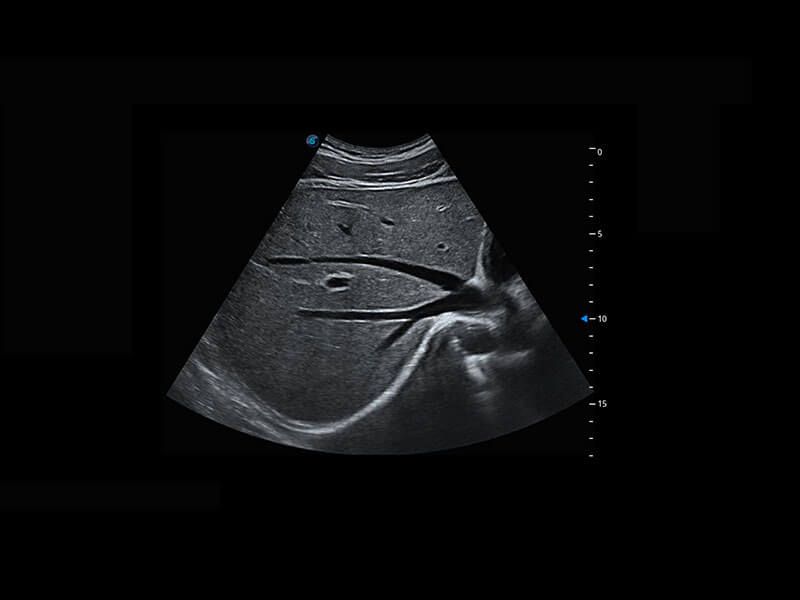

P60提供简单易学易用的高端诊断工具,为您中晚孕筛查提供快速清晰的解剖信息。

1 OFD(HC): 87.03 mm

HC: 251.00 mm

GA: 27w 1d

HC/AC: 96.13 %

2 BPD: 70.56 mm

GA: 28 w 2d

S-Fetus(acq.)

& S-Fetus(meas.)

S-Fetus

S-Fetus能够助您在实时扫查过程中自动识别标准切面、自动测量并录入报告。一个按键,即可快速、高效地获取胎儿生理指标,简化您的产科检查操作。